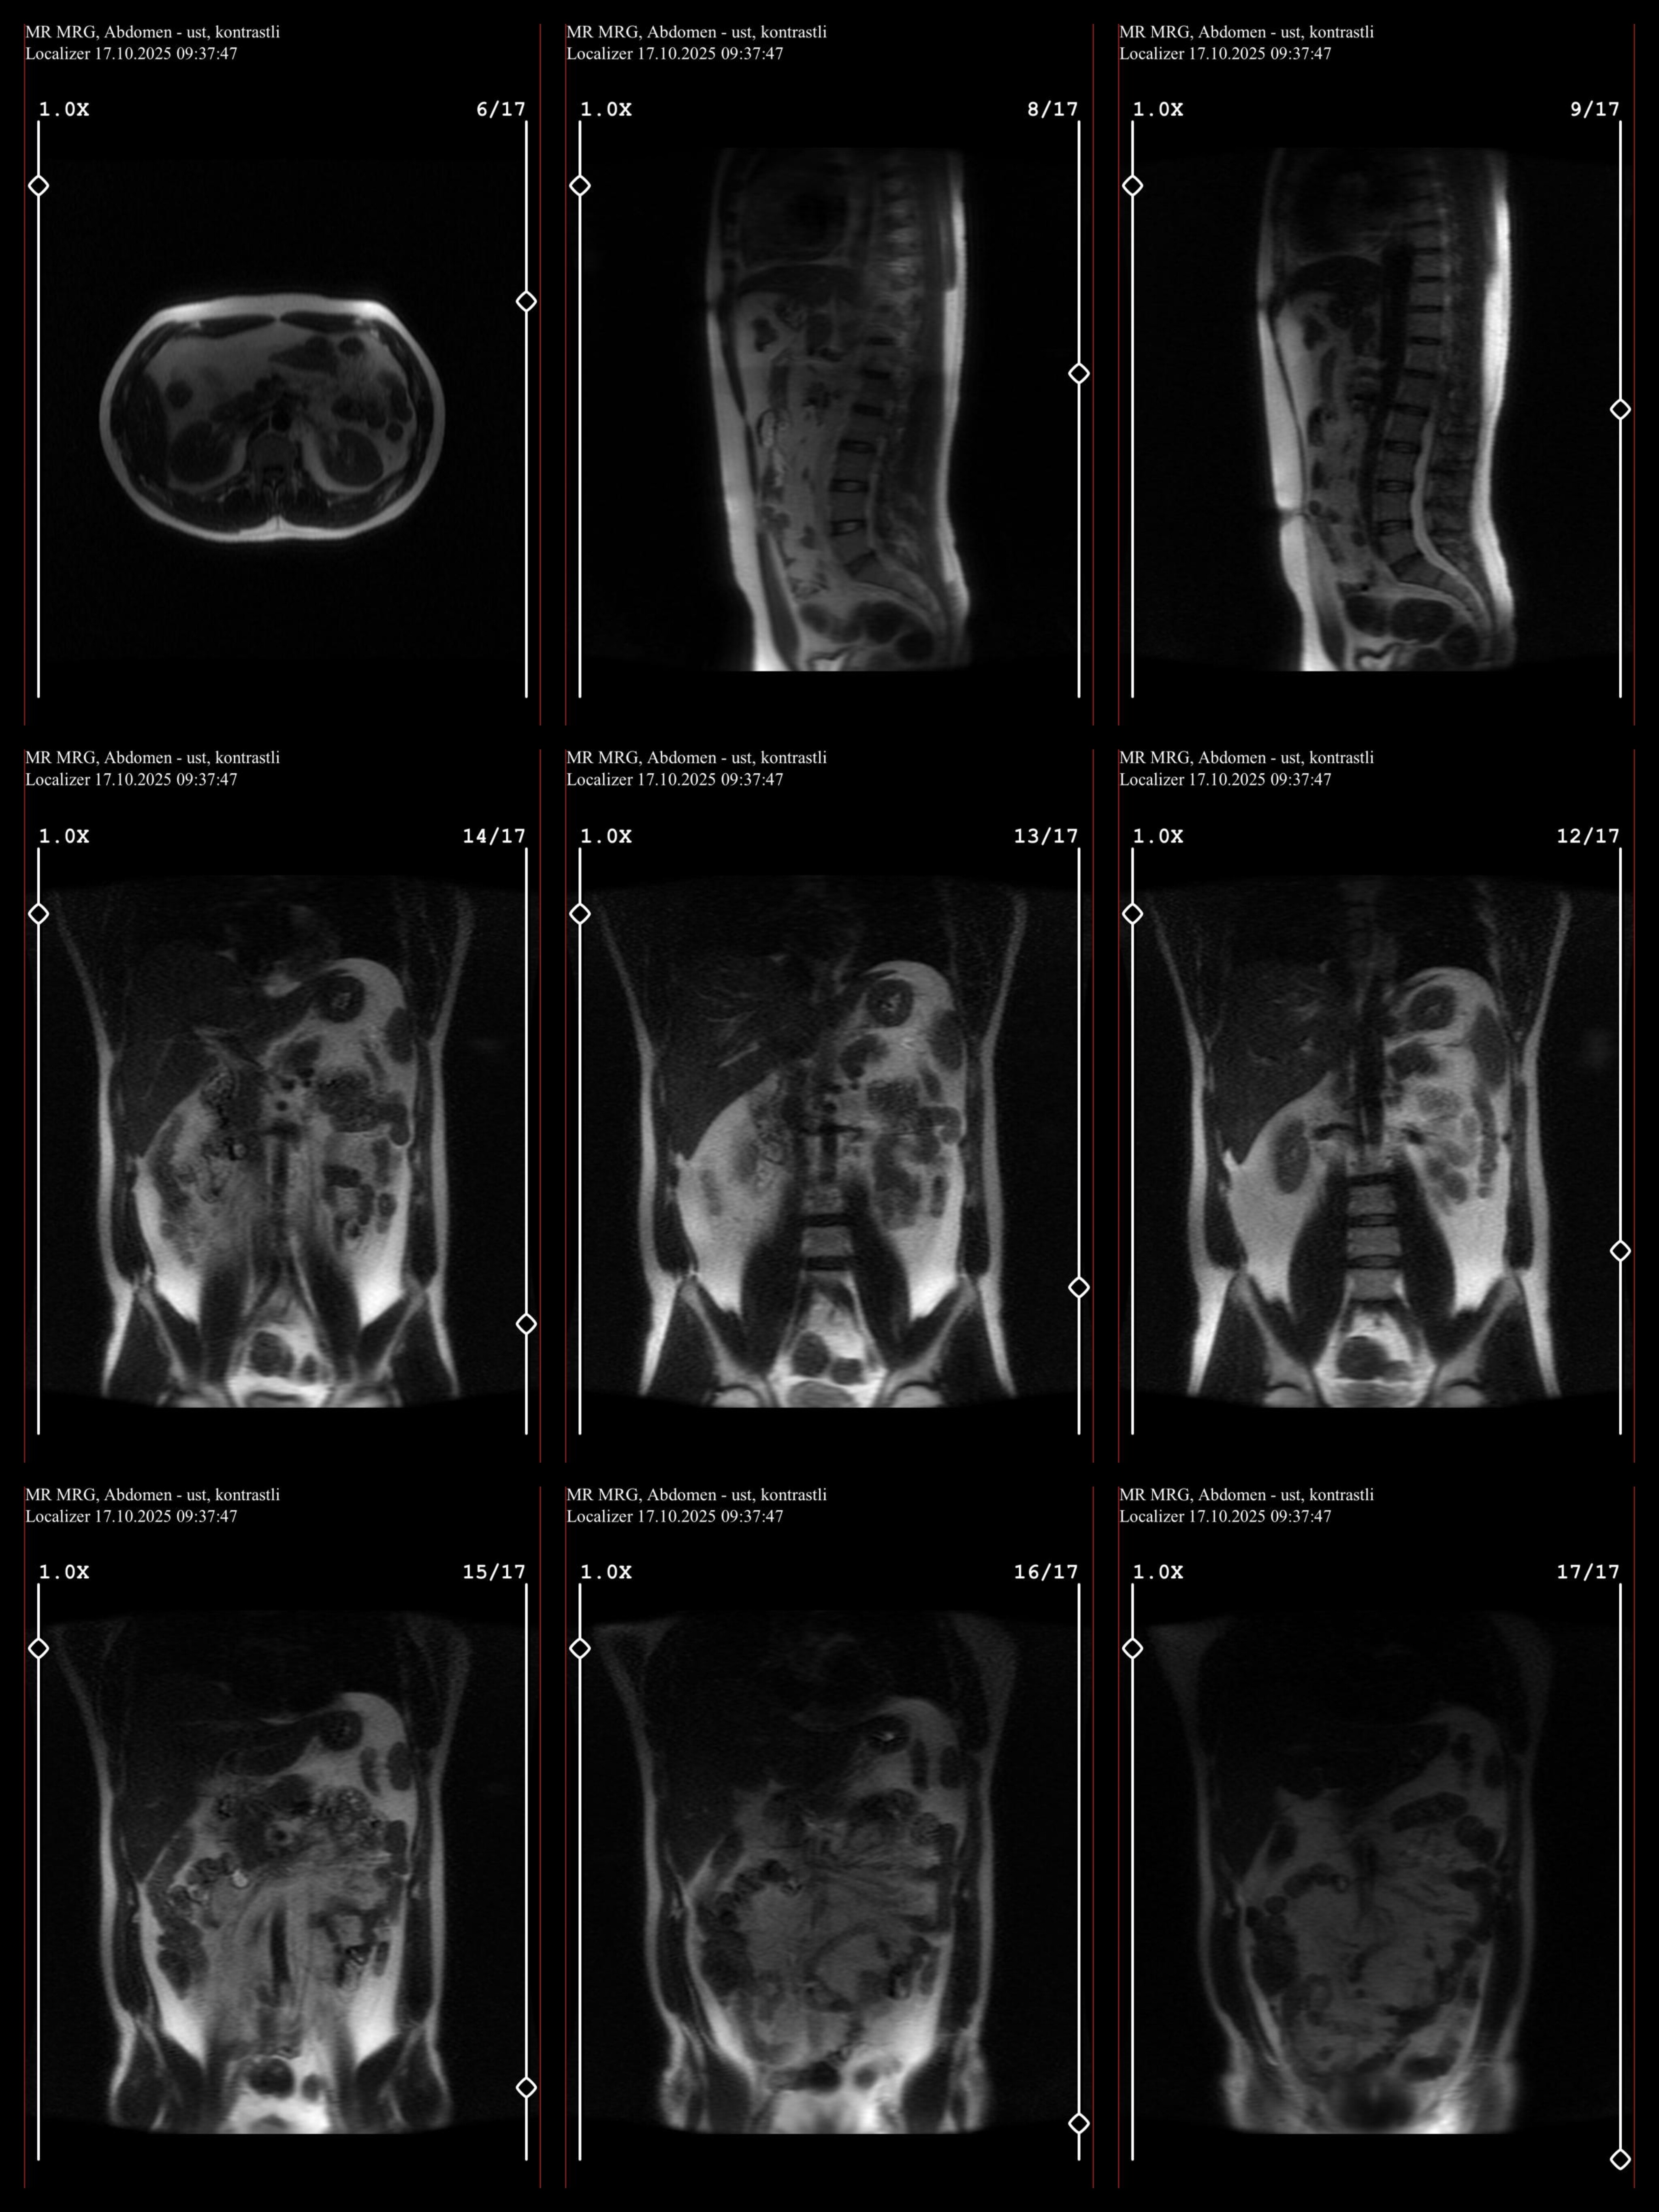

Hocam erkek 33 yaşında güvenlik için sağlık raporu almak için yapılmış Lenfoma olabilir demişler yorumlar mısınız

Herhangi bir rahatsızlığı yok sağlık raporu için gidip bunu söylüyorlar ama eminde değiller gastroenteroloji ve hemotoloji bölümüne yönlendiriyorlar parça alsınlar diye